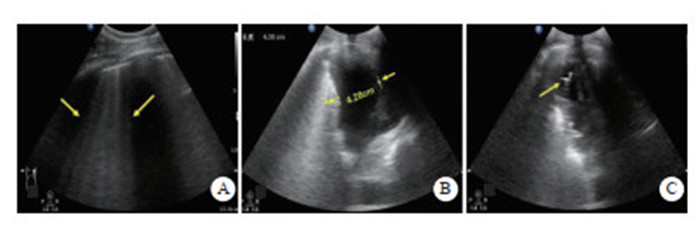

检查方法:采用高频(5.0~10.5 MHz)线阵超声探头。取仰卧位,头保持正中位,双眼睑闭合,眼球尽量固定。探头轻轻地放在闭合的眼睑上,避免过度施压。扫描切面分为横断面和矢状面。调整增益使视神经及其周围组织显示更加清晰。通常选择在眼球后3 mm的位置测量ONSD,测量时与视神经鞘的长轴垂直[27](图 2)。

|

| A: 视神经鞘探查体位及探头位置,A-1横切, A-2纵切;B:视盘的测量;C:视神经鞘的测量;D:颅高压时,ONSD水肿、增厚 图 2 超声测量视神经鞘直径 |

|

|